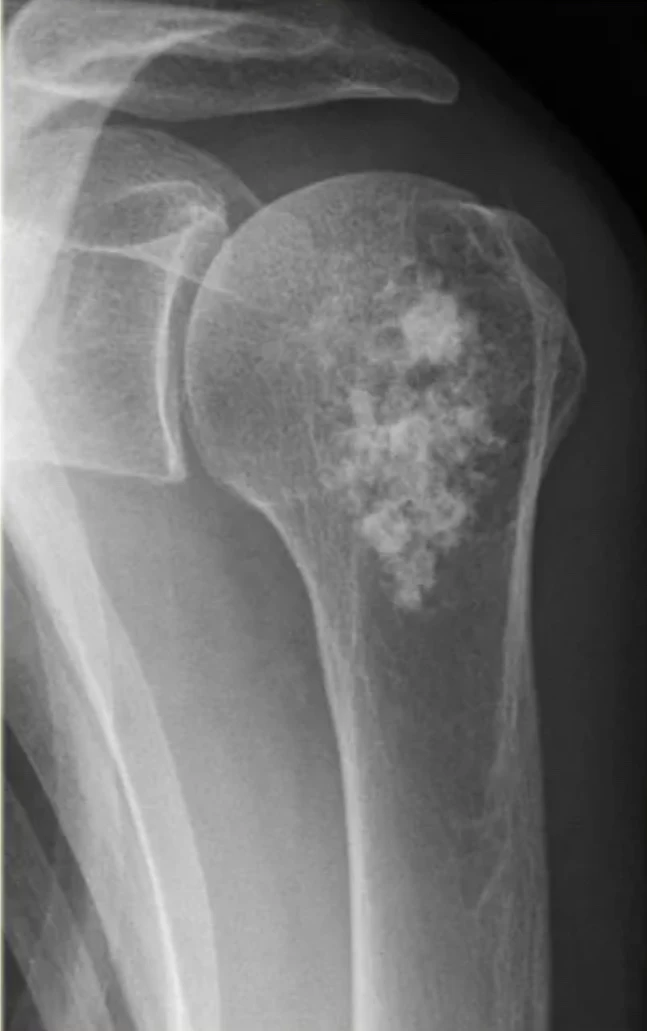

В основе инновационной разработки - радионуклид радий-223. Препарат «Ракурс, 223Ra» предназначен для лечения определённых видов онкологических заболеваний, преимущественно при метастазах в костях.

Радиоактивное излучение 223Ra целенаправленно воздействует на костные метастазы, уменьшая болевой синдром и улучшая качество жизни пациентов.